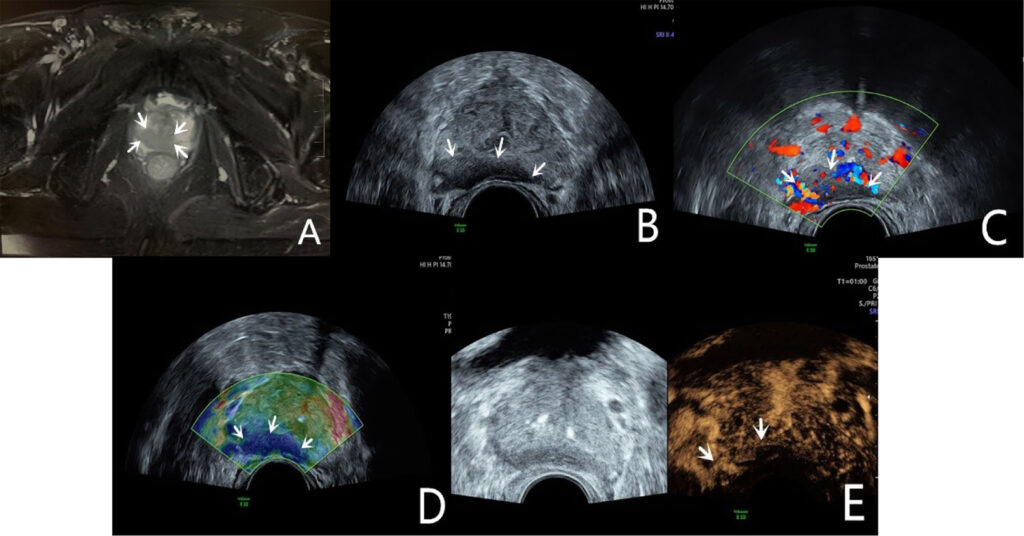

One of the most exciting aspects of prostate imaging today is the development of advanced ultrasound techniques to augment or go beyond conventional gray-scale TRUS. These include ultrasound elastography, contrast-enhanced ultrasound (CEUS) with microbubbles, and ultra-high-frequency micro-ultrasound. By providing new types of tissue information – such as stiffness or vascularity at the microvascular level – these modalities are improving the ability of ultrasound to detect and characterize prostate lesions. When used together, some have dubbed this approach as multiparametric ultrasound (mpUS), drawing an analogy to mpMRI. In this section, we explore each of these technologies, their evidence base, and how they are applied in prostate disease.

Ultrasound Elastography in Prostate Disease

Elastography is an ultrasound technique that measures tissue stiffness. The rationale in the prostate is straightforward: cancerous tissue tends to be stiffer than normal prostate tissue due to factors like increased cell density, fibrosis (collagen deposition), and loss of normal glandular architecture. This is the same principle that makes a hard nodule on DRE concerning for cancer – but DRE is subjective and can only assess the gland’s posterior surface. Ultrasound elastography, by contrast, can create an internal “stiffness map” of the whole prostate in vivo, potentially highlighting hard lesions within the gland that might represent tumors.

There are two main types of ultrasound elastography used in the prostate: strain elastography and shear-wave elastography.

- Strain Elastography (SE): This technique involves applying slight pressure (compression) with the transrectal probe and measuring the resulting tissue deformation (strain). Harder tissue deforms less under compression than softer tissue. The ultrasound system computes relative strain and displays an elastogram – typically a color map overlaid on the B-mode image where, for example, blue might indicate stiff areas and red soft areas (or vice versa). It’s a qualitative or semi-quantitative method; often the stiffness of a region is compared to adjacent “normal” reference tissue or to the overall gland. Strain elastography can identify a stiff lesion (e.g., a cancer) as a focal area of low strain (hard) within the softer surrounding prostate. It requires a steady hand and often multiple compressions to get a usable image. Early studies of strain elastography in prostate cancer showed that it can improve cancer detection when used alongside TRUS, with reported sensitivity around 70–82% and specificity 60–95%. A meta-analysis by Zhang et al. found pooled sensitivity ~72% and specificity ~76% for strain elastography in detecting prostate cancer, using prostatectomy specimens as reference. These numbers are an improvement over conventional B-mode alone. Elastography tended to have particularly high negative predictive value – one study reported an NPV ~95–99% when no stiff areas were seen on elastography (suggesting a low chance of missing significant cancer). However, strain elastography has limitations: it provides relative stiffness (so results can vary with how compression is applied), and the presence of large BPH nodules or calcifications can affect readings. It also doesn’t give an absolute stiffness value.

- Shear-Wave Elastography (SWE): This is a more quantitative method. In SWE, the ultrasound probe emits a focused acoustic radiation force impulse (ARFI) into the tissue, which generates shear waves that propagate through the prostate. The speed of these shear waves is measured – stiffer tissue allows faster shear wave propagation. The result is typically an absolute measurement of Young’s modulus (kPa) or shear wave velocity (m/s) for each small region, which can be color-coded on an image. SWE provides a quantitative stiffness map without needing manual compression. For instance, a prostate cancer might show a stiffness of 80 kPa versus normal prostate ~30 kPa. Several studies have demonstrated the performance of SWE. For example, Boehm et al.found that using a cutoff of 50 kPa for suspect areas yielded a sensitivity ~81% and specificity ~69% for significant cancer (with higher stiffness correlating with higher Gleason grade). Another study reported that with a cutoff of 35 kPa, they achieved negative predictive value of 96% – meaning if the prostate had no area stiffer than 35 kPa, significant cancer was very unlikely. A 2019 meta-analysis (Yang et al.) concluded that SWE could be a “feasible technique to ameliorate PCa detection” and potentially reduce unnecessary biopsies. Furthermore, elasticity correlates with tumor grade: higher Gleason cancers tend to be stiffer. In one series, Gleason 6, 7, and ≥8 tumors had mean stiffness of ~92, 102, and 132 kPa respectively, showing a clear stepwise increase. This opens the possibility that elastography not only detects cancer but might help assess its aggressiveness noninvasively.

Elastography can be particularly helpful for cancers in the anterior fibromuscular stroma or deep transition zone, which are hard to visualize on B-mode but can be detected as focal stiff areas. It also may help distinguish benign stiff entities (like calcified BPH nodules) from cancer: BPH nodules can be firm but often not as uniformly stiff as cancer and have different elastographic patterns. However, overlap exists, and absolute diagnosis by elastography alone is not currently possible – it’s a complement to imaging and biopsy, not a replacement.

One challenge in implementing elastography widely has been the lack of standardization. Different machines have different scales and techniques (some use strain ratio calculations, others provide kPa values). There is also a learning curve to interpreting elastograms. Despite this, numerous studies validate that elastography significantly improves prostate cancer detection when added to TRUS, and can guide targeted biopsies. A recent (2025) review by Liang et al.concluded that ultrasound elastography has “significant advantages in diagnostic accuracy” for prostate diseases compared to conventional methods, though it noted the need for standardized protocols and broader availability of equipment. Elastography is also being investigated for treatment monitoring – for example, after focal therapy or radiation, elastography might detect residual stiff tumor versus softened treated tissue.

In summary, ultrasound elastography provides a virtual “finger” to palpate the prostate from the inside, mapping stiffness to highlight suspicious areas. It has shown improved detection of clinically significant cancers in many studies and is an exciting addition to the sonographer’s and urologist’s toolkit. As the technology matures and becomes more standardized, elastography could be routinely integrated into prostate ultrasound exams to decide where to biopsy or whether a patient can safely avoid biopsy (if the gland is entirely soft and unremarkable on elastography, for instance).

Contrast-Enhanced Ultrasound (CEUS) and Microbubble Imaging

Another major advance in ultrasound is the use of microbubble contrast agents to visualize blood flow and perfusion in the prostate. Tumors typically induce abnormal microvascular patterns – they often have increased blood flow and chaotic vessel architecture due to angiogenesis. Conventional Doppler ultrasound is not very sensitive to slow flow in small vessels, but microbubble contrast can overcome that limitation by enhancing the ultrasound signal from blood.

In CEUS, a contrast agent consisting of microscopic gas-filled bubbles (encased in a lipid or protein shell) is injected intravenously. These microbubbles circulate and reflect ultrasound strongly, allowing real-time visualization of blood perfusion in tissues. In the prostate, a malignant tumor will often demonstrate enhanced contrast uptake (appearing as a focal area of rapid contrast wash-in and wash-out) compared to normal tissue. By observing the contrast kinetics (usually over a few minutes after injection), one can generate Time-Intensity Curves (TIC) for regions of interest. Parameters like Time to Peak (TTP) enhancement, Peak Intensity, Wash-in rate, and Area Under Curve can be quantified. Tumors tend to show a shorter time-to-peak and higher peak intensity (reflecting quicker and greater filling due to neovascularity). For instance, a study by Zhu et al. found that higher grade prostate cancers had a significantly shorter contrast arrival time and time-to-peak, as well as a higher peak intensity than lower grade tissue. This makes intuitive sense: aggressive cancers have more leaky, high-flow vessels that light up earlier on contrast.

CEUS of the prostate is typically performed transrectally simultaneously with B-mode imaging. The microbubbles remain within the vasculature (they do not leak into interstitium), so what is seen is essentially a map of blood volume and flow in the prostate. A cancer might stand out as an “early and bright” enhancing focus. Some cancers, however, especially small or less angiogenic ones, might not show a big difference. Also, inflammation can cause increased blood flow and mimic tumor on CEUS. Nonetheless, multiple studies have shown CEUS-targeted biopsy improves cancer detection. As mentioned earlier, adding CEUS guidance to systematic biopsy increased cancer detection rates by a few percent in some trials. Mitterberger et al. (one of the early pioneers of prostate CEUS) reported that contrast-targeted biopsies could detect ~10% more cancers after an initial negative biopsy round. A 2017 meta-analysis found that CEUS-targeted biopsy had a higher detection rate for clinically significant cancer than systematic biopsy alone, though results varied by study. In absolute terms, sensitivity of CEUS in detecting prostate cancer lesions is around 59–81% with specificity ~70–88%according to a systematic review of parametric ultrasounds. These numbers indicate a notable improvement over unenhanced ultrasound, though not as high as MRI. CEUS particularly shines in identifying hypervascular tumors in the peripheral zone. In the transition zone, BPH nodules can also enhance, which may reduce specificity (one analysis noted CEUS sensitivity ~58% and specificity 70% in peripheral zone, versus 38% sensitivity, 79% specificity in the transition zone).

Multiparametric Ultrasound (mpUS) Combination

As with MRI, where multiple sequences are combined (T2, diffusion, etc.) for better accuracy, the concept in ultrasound is to combine modalities to improve overall diagnostic performance. We have touched on this by noting that elastography and CEUS each improve detection, and Doppler adds information too. The term “multiparametric ultrasound (mpUS)” has been used to describe combining two or more of these ultrasound techniques during one exam. For example, an exam might include B-mode, color Doppler, strain elastography, and contrast enhancement together. Each modality might catch some cancers the others miss.

A 2020 systematic review by Postema et al. examined how various ultrasound methods could be combined for prostate cancer detection. It found that using multiple ultrasound parameters together improved diagnostic accuracy. In practical terms, one might first scan with gray-scale (find any hypoechoic lesions), then check those areas with Doppler (is there increased flow?), then perform elastography (are they stiff?), then inject contrast (do they enhance quickly?). A lesion that is suspicious across multiple parameters (e.g. hypoechoic, hypervascular, stiff, and shows contrast uptake) is very likely to be clinically significant cancer. In contrast, a finding that only triggers one parameter might be less concerning (for instance, a mildly hypoechoic area that is soft on elastography and no contrast uptake is probably not cancer). Combining modalities also improves confidence in negative results – if the entire gland is unremarkable on B-mode, has no focal stiffness, and no focal contrast enhancement, the chance of missing a significant cancer is quite low.

The previously cited 2024 systematic review by Jawli et al. in Cancers journal quantified some of this. It reported that while gray-scale TRUS alone had sensitivity ~38–55%, and single techniques like SWE or CEUS individually had sensitivities in the 55–88% range, a combined multiparametric ultrasound approach achieved sensitivity about 74% for overall cancer detection (with specificity ~59% in that analysis). For clinically significant cancers, mpUS sensitivity was similarly ~74%, notably higher than TRUS alone (~55%). In essence, mpUS lifted the detection closer to what mpMRI accomplishes. The trade-off was specificity; with multiple parameters you catch more true cancers at the expense of more false positives (hence specificity ~59%). But in cancer screening, a higher sensitivity is usually the priority – one can always perform a biopsy to sort out false positives.